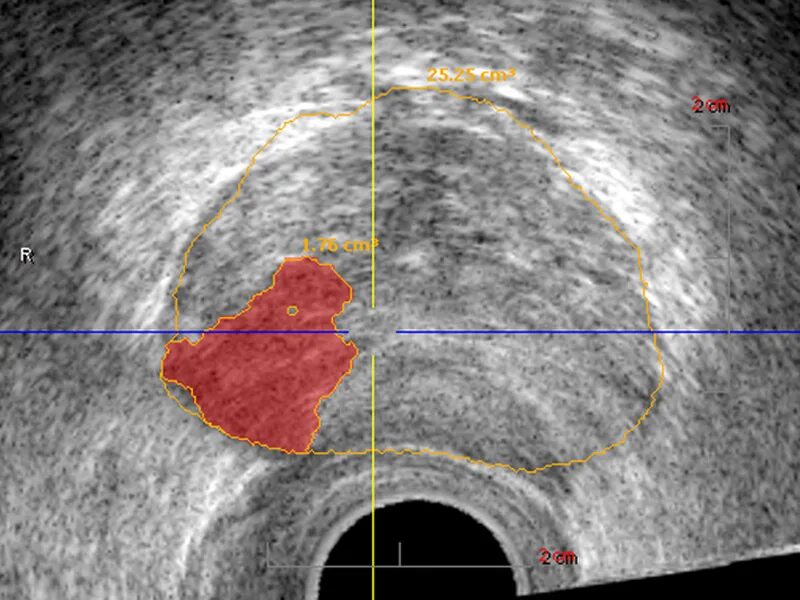

Бактериальная простата